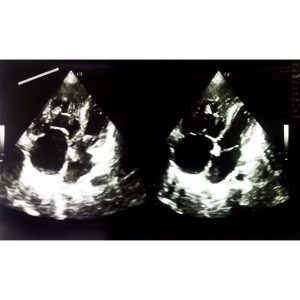

当院では胸部症状のある患者さんに対して循環器内科専門医の私が心臓超音波検査を施行しています。

心臓超音波検査では三尖弁の逆流から求めた圧格差から、推定右室収縮期圧(推定肺動脈収縮期圧)を計算し、40mmHg以上で肺高血圧症を疑っていきます。